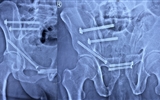

兰大二院完成甘肃省首例徒手全通道螺钉治疗骨盆前后环分离伴前柱骨折微创手术